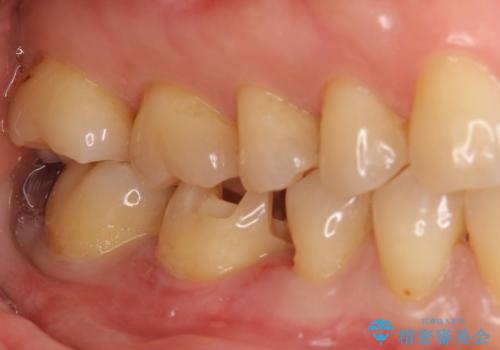

銀歯を白く セラミックインレーに

- 銀歯にしたのが20年以上前とのことで、白くやりかえたいということでした。

セラミックインレーにしています。

- 7万円(左下6 emaxプレスインレー 7万円)費用は治療当時の料金となります

銀歯を外して、下に虫歯があればしっかり取ります。しみるなどの症状が出る前がおすすめです。